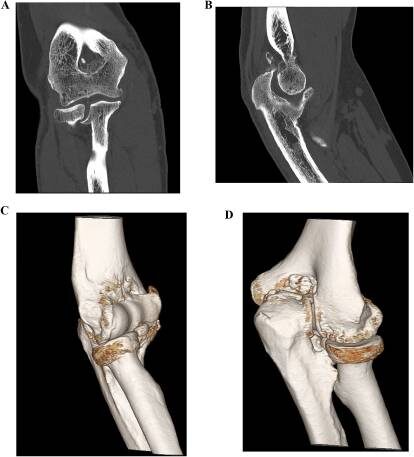

📌 КТ (компьютерная томография) - в сложных случаях;

-2